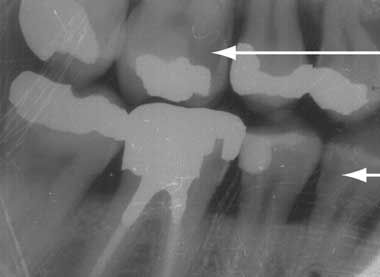

Although caries is the most common cause of pulpitis and periapical spread of infection, there are other conditions that cause dentofacial pain. The most common are occlusal trauma, tooth fractures and cracks. Some infections are iatrogenic. GPs should be aware of caries as a cause of dental pain, but they should also be aware that not all carious lesions appear as cavities in teeth, particularly in this era of water fluoridation (Box 2, Case 2). Sometimes caries will show simply as an area of greyish discolouration or may only be visible on x-ray (Box 3).

Case 2: Diagnosis overlooked because of intact enamel

A middle-aged woman presented to her GP complaining of pain of a week’s duration in the left aspect of the maxilla. The pain was a dull ache, intermittent but becoming progressively worse. The patient had avoided eating on the left side since the onset of pain.

On examining her teeth, the GP could not identify any cavities and accordingly excluded a dental cause of pain. The doctor prescribed paracetamol + codeine and suggested review in a week’s time.

The patient returned 3 days later with severe pain and minor facial swelling on the left side. Oral examination revealed no cavities in the left upper teeth, but a slight greyish shadow was noted on the left upper first molar. The tooth was percussed with a tongue depressor to reveal acute tenderness. A diagnosis of caries with extension into the periapical tissues was made and later confirmed by x-ray (see image in this Box).

Ideal management: Suspected caries beneath intact enamel requires pain control and immediate referral to a dentist. Antibiotics are only indicated if there are systemic symptoms, if there is fear of spread to vital structures such as the eyes or floor of the mouth, or if dental treatment cannot be obtained immediately.